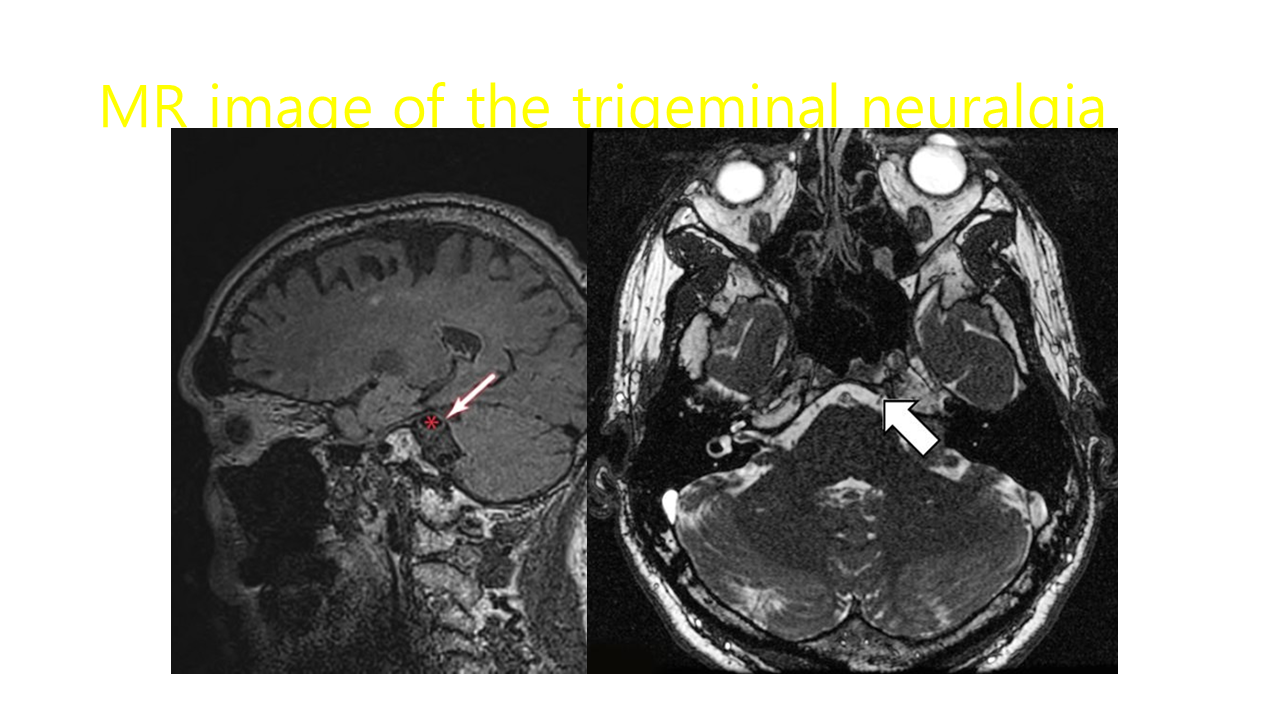

삼차신경 분포 영역에서 대개 편측성으로 나타나 수 초 또는 수 분간 지속되는 찌르는 듯한 양상

의 재발성 통증이 특징입니다.

삼차신경통의 통증은 얼굴을 만지거나, 면도, 대화, 양치 등과 같은 비통증성 자극에 의해 나타나며 발통대(trigger zone)가 존재할 수 있습니다.

삼차신경통은 삼차신경의 하나 이상의 분지에 나타나며 주로 삼차신경의 상악 분지 및 하악 분지에 많이 나타나고 안분지에 나타나 는 경우는 흔하지 않습니다. 분지별 발생 빈도는 상악분지, 하악분지, 안분지 순이며 안분지에서 발생하

는 경우는 4~7%로 가장 드물다고 알려져 있습니다.